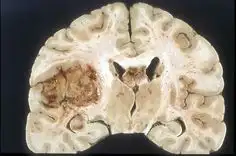

1. 교모세포종은 중추신경계의 신경교세포에서 시작되는 암으로, 뇌 조직을 지지하고 보호하는 역할을 합니다.

3. 교모세포종은 빠르게 성장하며 뇌의 여러 부위로 침투하는 경향이 있습니다. 초기 증상으로는 두통, 메스꺼움, 구토 등이 있습니다.

교모세포종은 뇌의 다양한 부위에 발생할 수 있으며, 그 위치에 따라 증상이 달라질 수 있습니다.